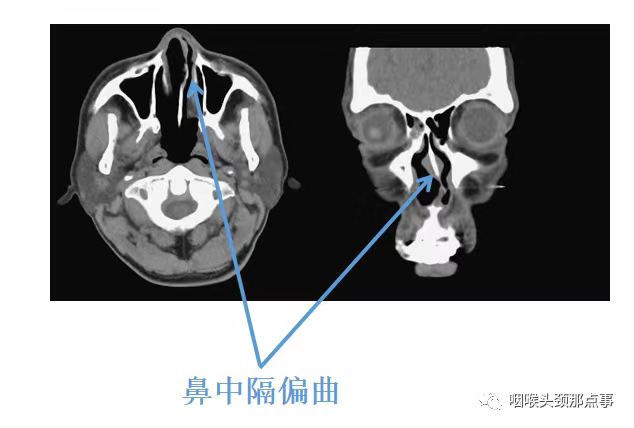

近十年一直被打呼、夜间憋气困扰的孙先生来到我的门诊,他和我说的最多的就是夜里鼻塞的厉害,翻身频繁,总感觉一侧睡时间长了就鼻腔堵得慌,最让他困扰的是鼾声特别大,老伴都不愿意和他在一个房间睡觉;还有近几年心脏也不舒服,检查发现有房颤,一直在吃抗凝药。给他做了初步检查发现他鼻中隔左偏特别明显,鼻甲也比较肥大,检查口咽发现他软腭稍有下垂,他今年68岁,肌肉松弛、张力下降也是一方面原因,其他平面没有特别狭窄;做了多导睡眠监测提示AHI指数18.6,最低血氧69%,他属于中度阻塞性睡眠呼吸暂停重度低通气综合征,应该与鼻腔平面阻塞关系较大;考虑患者一直服用抗凝剂,手术后出血风险较大,给他试用CPAP,也就是呼吸机,由于鼻腔平面阻塞,患者呼吸机耐受性很差,坚决要求手术治疗。经过综合评估,暂停长效抗凝剂,调整为短效抗凝治疗后患者做了鼻中隔偏曲矫正术及鼻腔扩容手术,为了安全起见,鼻中隔术后做了贯穿缝合,下鼻甲消融后也做了充分的止血,同时又做了鼻腔填塞。三天后患者鼻腔填塞物完全取出,当天晚上患者打呼就基本消失了,自己平时心脏不适也明显改善。出院后患者在我好大夫上给我留言和我说,现在夜间睡眠安静很多,恢复的很好,这是一个非常典型的鼻腔阻塞导致的阻塞性睡眠呼吸暂停综合征的患者。

首先就是如上面所讲的鼻中隔偏曲,鼻中隔偏曲在人群中很常见,这是由于人体结构在生长发育过程中不平衡有关,每个人多多少少鼻中隔都会有点偏曲,一般没有明显症状;但是如果偏曲明显,就会出现结构性鼻炎,也就是说鼻中隔向一侧偏曲时,由于偏曲侧空间狭窄,另一侧相对空间较大,但是人体为了保持平衡,空间较大侧鼻腔的鼻甲会出现代偿性肥大,从而导致患者双侧鼻腔均出现明显的阻塞,鼻甲有鼻甲周期,我们夜间经常翻身就是鼻甲周期发挥了重要作用,也就是说我们向哪个方向卧位,同方向的鼻甲会肿大,比如我们向右侧卧位,右侧鼻甲会变大,促使我们不自主的向左侧卧位,如此反复,促使我们夜间睡觉时翻身,避免夜间长期一个姿势睡觉。一般人这种鼻甲周期是没有感觉的,不会有鼻塞症状,但是对于有鼻炎的患者,他们就能明显感受到这个周期所带来的的困扰,会感觉鼻塞,这也就是为什么孙先生夜间会频繁翻身、鼻塞、憋气的原因。

鼻中隔偏曲